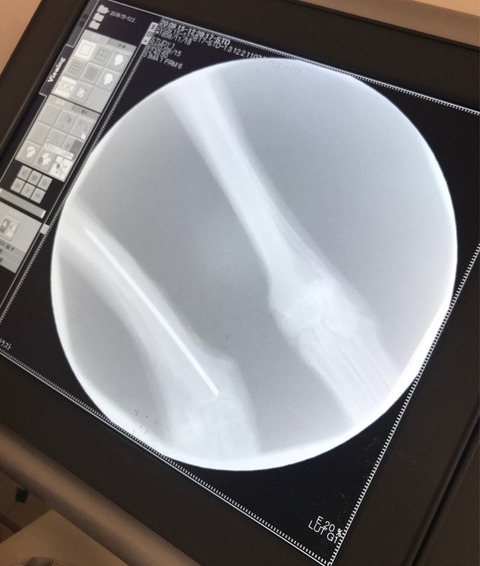

下は骨折箇所の診断です、見ただけで前足が骨折していたのが分かります。

ところが 犬を渡された時 右後ろ足が骨折してプレートが入っていますと幹事さんの説明が動画にも入っています。💦

ちゃんと見てないのがバレバレです。💢